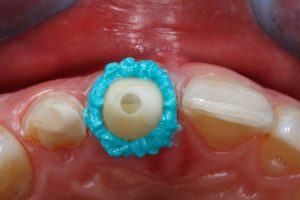

Dabei überzeugt die Retraktionspaste nicht nur im Ergebnis, sondern auch mit ihrem Handling: So gibt die Farbe einen guten Kontrast zur Gingiva, was insbesondere die Arbeit an schwer einsehbaren Stellen erleichtert. Dank der sehr schmalen und leicht biegsamen Kanüle lässt sich das Material sowohl gut dosieren als auch applizieren. Hierbei ist die Paste leicht auszudrücken und punktet anschließend mit einer sehr guten Fließviskosität bei gleichzeitiger Standfestigkeit zur Eröffnung des Sulkus.Bei der Applikation füllt die adstringierend wirkende, aluminiumchlorid haltige Paste temporär den Sulkus, stoppt etwaige Blutungen und verdrängt Feuchtigkeit.

Die VOCO Retraction Paste lässt sich einfach und hygienisch direkt aus dem SingleDose Cap, einer Eigenentwicklung von VOCO, in den Sulkus applizieren. Vorteile der SingleDose: Jeder Patient erhält sein ganz eigenes Präparat. Drittkontakte und weitere Kontaminationsmöglichkeiten werden so auf einfachem Wege unterbunden.

Dabei ist das SingleDose Cap mit handelsüblichen Composite-Dispensern wie beispielsweise dem VOCO Caps Dispenser kompatibel und reicht für bis zu 3 Sulki.